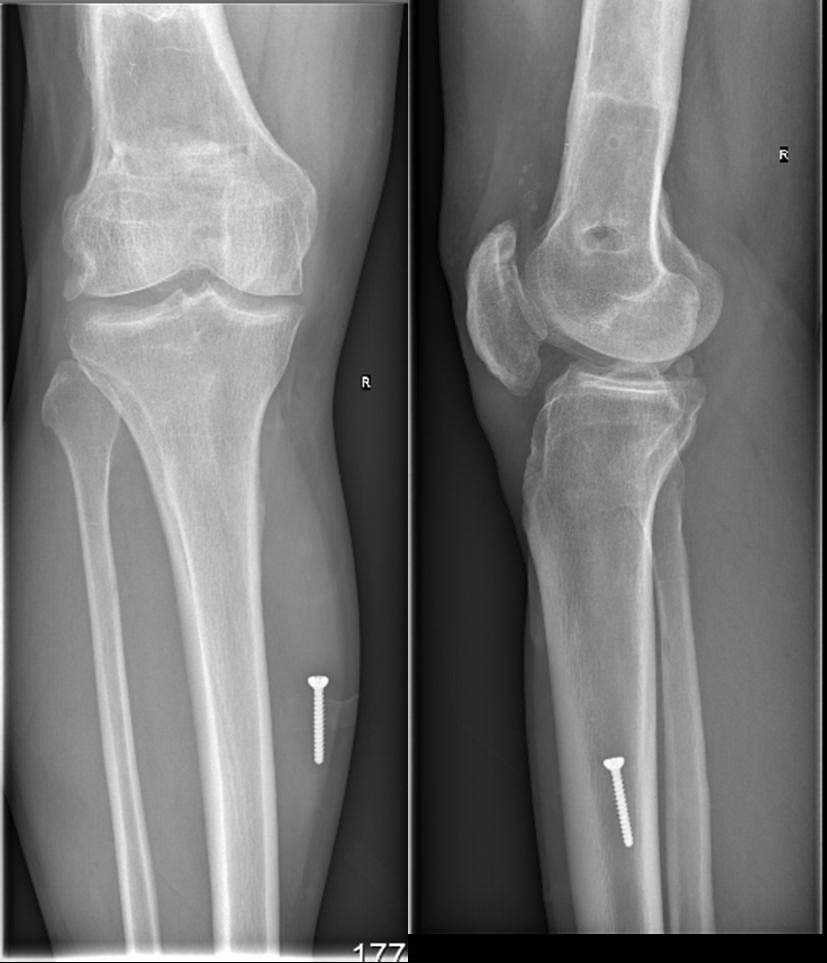

Пациент, мужчина, 45 лет. В 1982 году получил закрытый перелом диафиза бедренной кости справа. Результат консервативного лечения-варусная деформация бедренной кости В 1987 году выполнена вальгусная корригирующая остеотомия на уровне дистального эпифиза бедренной кости: варус бедренной кости нивелирован. Но в процессе лечения сформировалась выраженная контрактура в правом коленном суставе. Производилось 2 раза агрессивная разработка правого коленного сустава в аппарате типа Илизарова. В настоящее время беспокоят боли в области правого надколенника, при длительной ходьбе появляется ощущение скованности в 4-х главой мышце бедра, при отрыве правой стопы, голень и стопа как бы выбрасывается вперед (пациент, при этом, процесс разгибания в коленном суставе плохо контролирует). Правый коленный сустав внешне не деформирован, не отечен. Объем движений: сгибание до 90 градусов (до прямого угла, разгибание полное_180 гр. Сустав стабилен во всех плоскостях. Надколенник расположен практически на уровне суставной щели (тибиа-феморальной), малоподвижен, так называемая «игра надколенника» у пациента резко снижена . Пациент поступил в наше отделение для выполнения операции в объеме эндопротезирования правого коленного сустава. Однако, оценив коленный сустав, мы засомневались в необходимости данной операции этому пациенту. В данном случае , низкое стояние дегенеративно измененного правого надколенника нарушает функцию разгибательного аппарата правого коленного сустава и основная причина сосредоточена здесь, в надколеннике (по нашему мнению). У меня вопрос к коллегам: как деликатно, на нарушая разгибательный аппарат, помочь пациенту? Какие виды реконструктивных операции предпочтительны. С уважением Шушания Батал, ФБУ 3 ЦВКГ имени А А Вишневского

винт, видимый на рентгенснимках, фиксирован к коже пациента лейкопластырем при рентгенографии рентгенлабарантом, используется для калибровки рентегнснимка при планировании операции эндопротезирования.

У вашего больного синдром Patella Baja или Patella Infera, т.е. низкое расположение надколенника. Состояние встречается в результате травмы или послеоперационных осложнении, например после коррегирующих операции. Сравнительные снимки показывает, что правый надколенник почти касается большеберцовую и укорочение связки приводит к нарушению пателло феморального взаймотношения. В результате такого нарушения начинается хондромаляция хрящевого покрова.

спешу поделиться результатом операции, проведенной 25/01/2012 года. Выполнен передний срединный доступ к коленному суставу длиной до 8 см, полость коленного сустава вскрыта медиально от надколенника, выделилось до 20 мл синовиальной жидкости. Надколенник вывернут. Суставная поверхность надколенника склерозирована,

резко слерозирован (до каменной плотности) верхне-наружный квадрант наколенника. Хрящ на надколеннике практически отсутствовал. Остеофиты по всей окружности надколенника (надколенник имел вид "блюдца" из-за этих сотеофитов). Жировое тело гипртрофировано. Хрящ на мыщелках бедра достаточно сохранный, хотя не идеальный. В межмыщелковом простарнстве бедра (спереди крестообразных связок)остефиты.